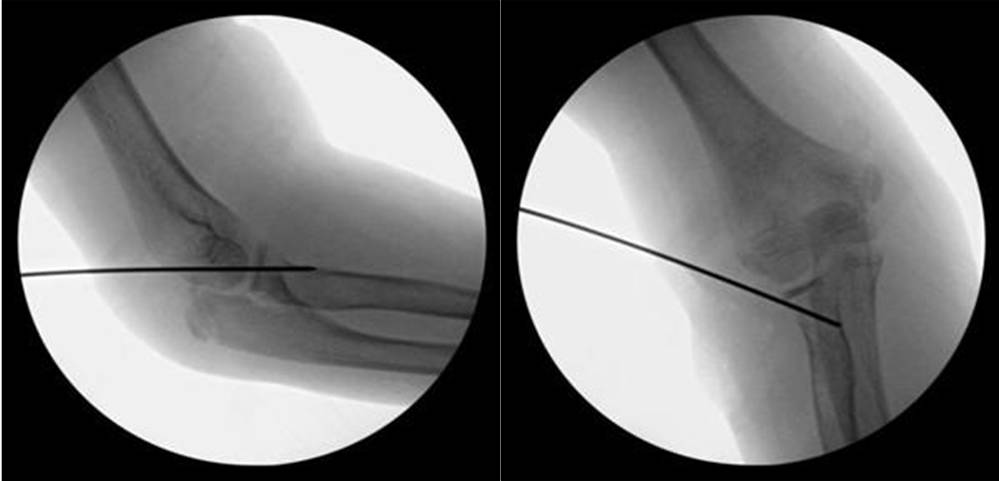

经外侧入路进行肘关节造影术的进针点及进针方向,解剖标志 1- 肱骨外侧髁,2- 桡骨头,3- 尺骨鹰嘴

7 岁患者发生桡骨颈移位性骨折,肘关节造影术术中前后位透视可见关节线,并可帮助骨折获得满意复位(造影相关文字及图片摘引:Nowicki 关节造影术在小儿骨科的应用.林超文译)